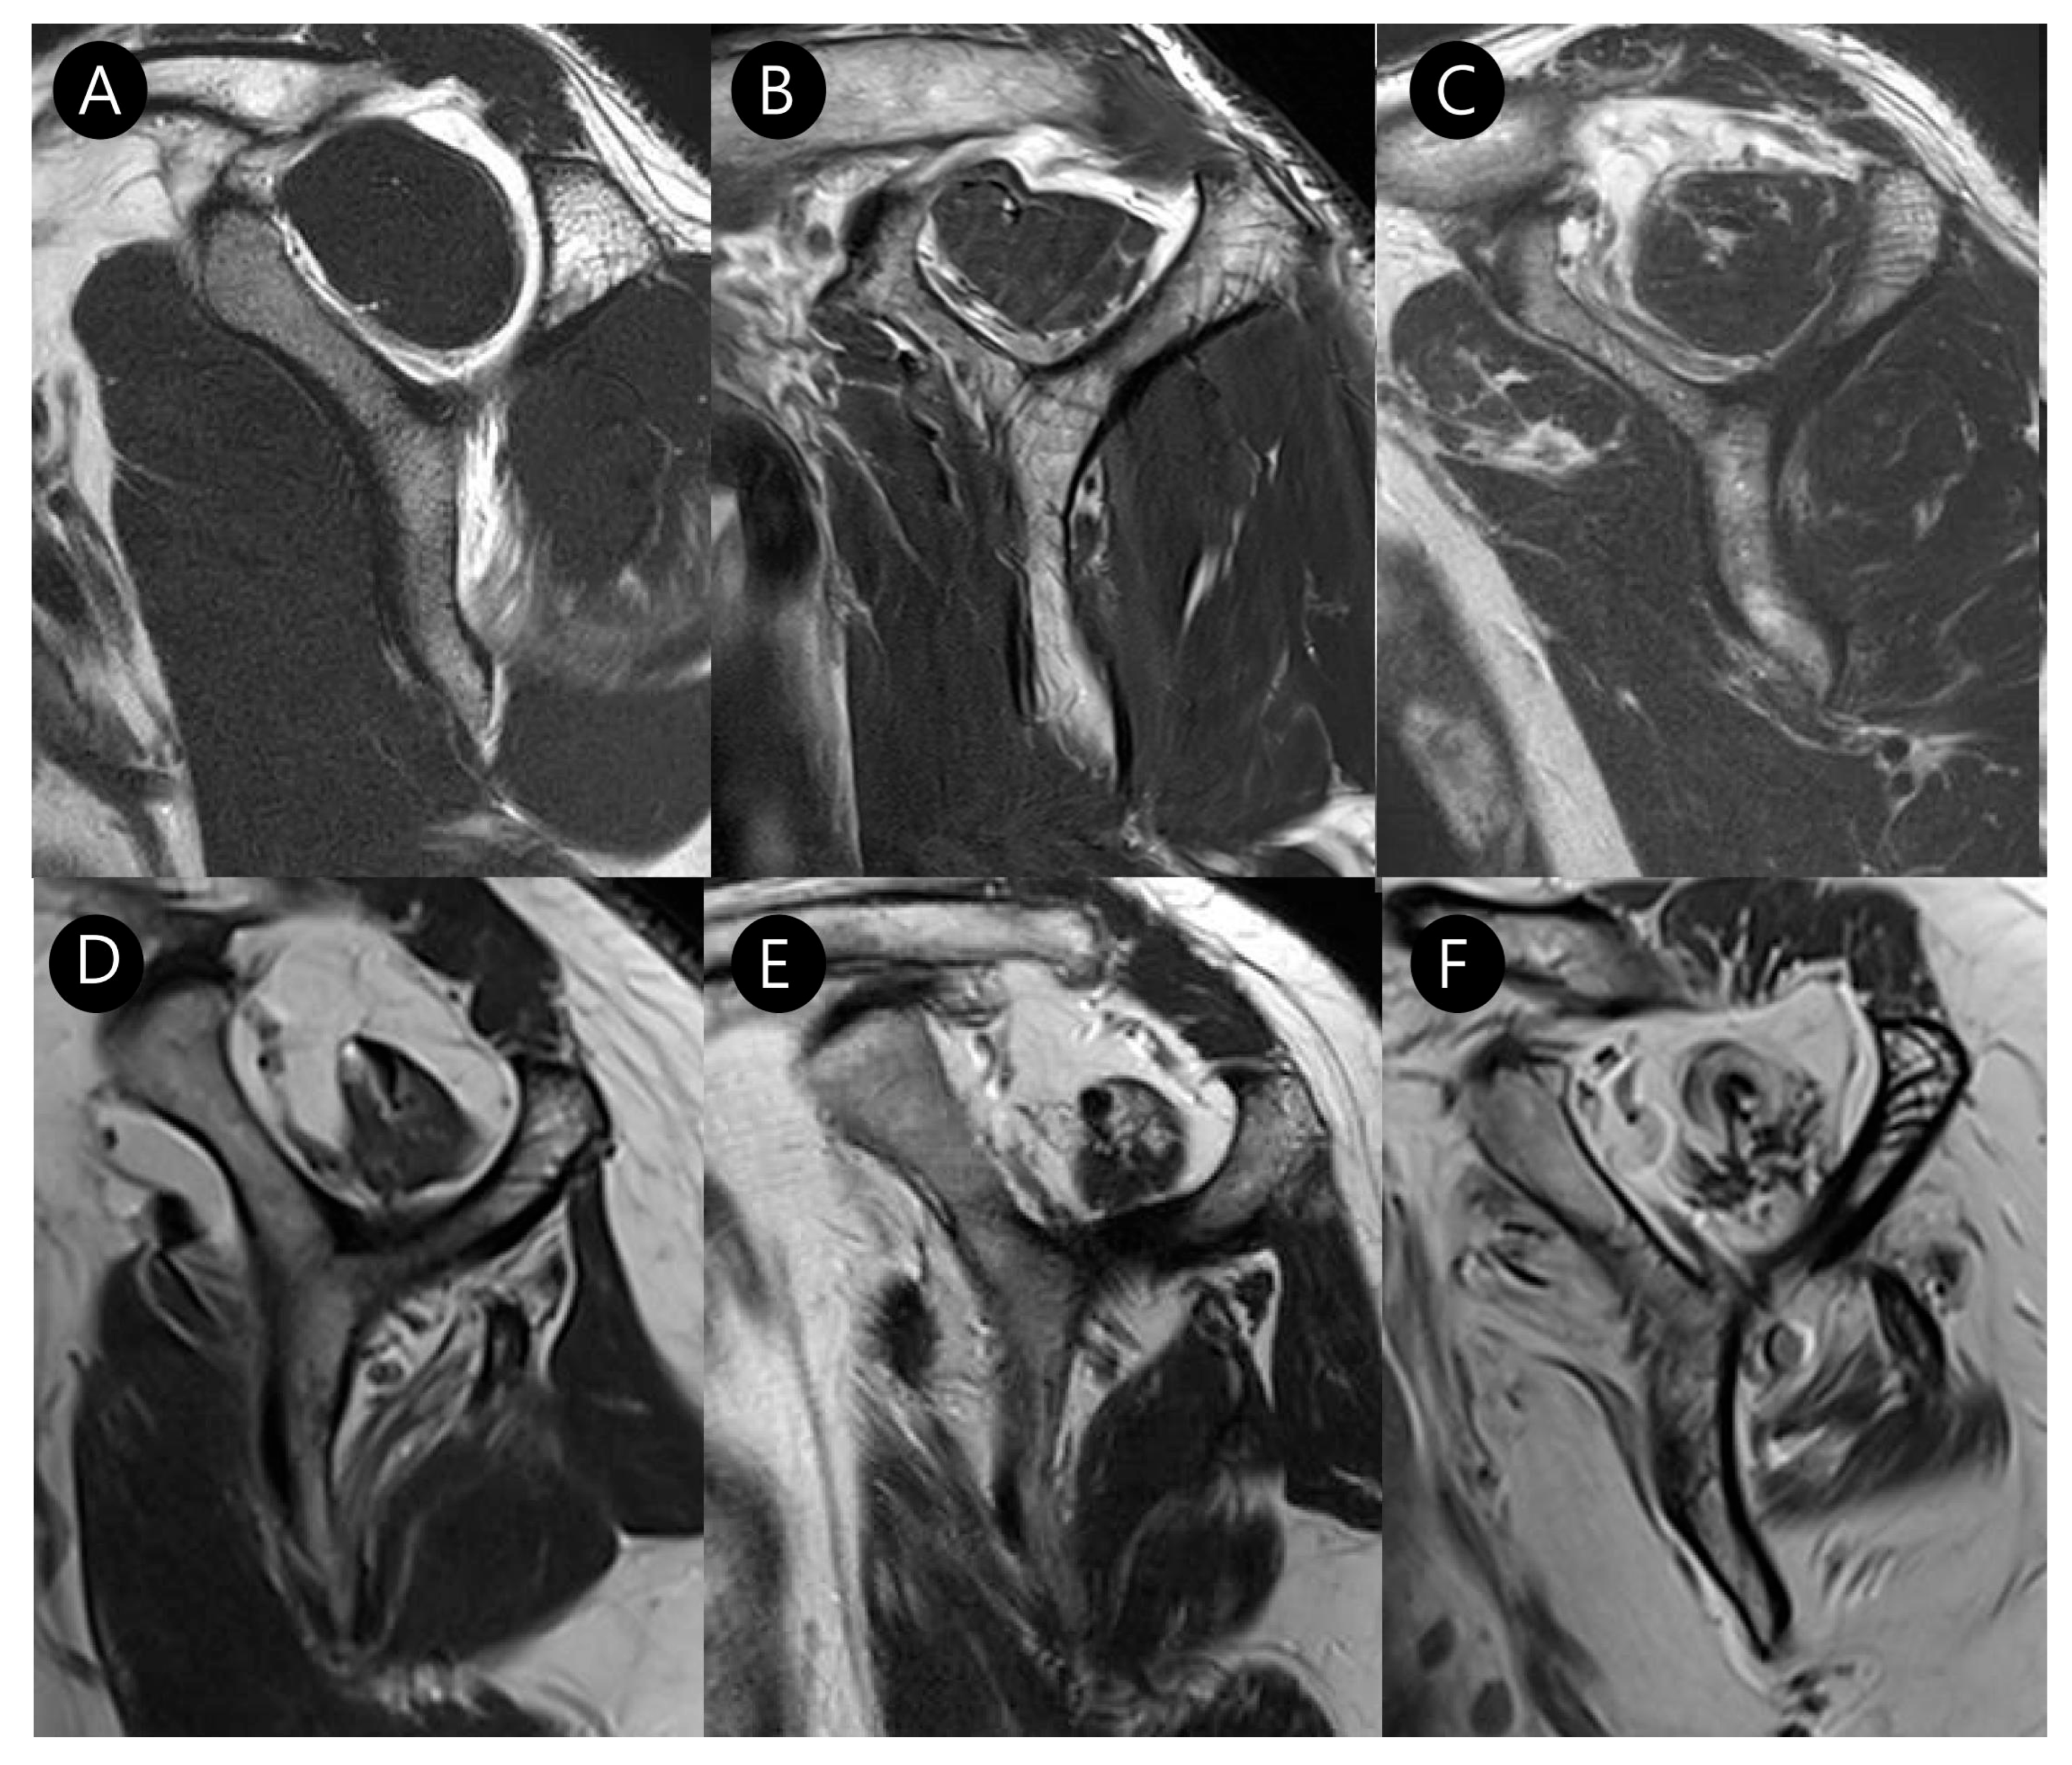

On multivariate logistic regression analysis, however, only subscapularis muscle atrophy (OR, 33.830; 95% CI, 2.505–456.914; p = 0.008) and LHBT subluxation (OR, 22.836; 95% CI, 3.993–130.605; p < 0.001) remained as independent predictors of Yoo type IIB lesions. The multicollinearity of the independent variables in the logistic regression model was assessed using the variance inflation factor (VIF). All predictor variables showed low VIF (<2), indicating a general absence of multicollinearity, except for LHBT subluxation/dislocation, which exhibited a VIF of 6.75. The detailed results are summarized in Table 5. Representative MR images from the control and study groups are presented in Figure 8.

Figure 8.

Representative MR images of Yoo type IIA (A–C) and IIB (D–F) subscapularis tendon (SSC) tears: (A) T2-weighted oblique sagittal fat-suppressed image in a patient with a Yoo type IIA lesion demonstrates a partial thickness tear of the SSC with ≤50% detachment from the first facet (arrow). (B) T2-weighted oblique axial fat-suppressed image shows an intact long head of the biceps tendon (LHBT, arrowhead) in the bicipital groove. (C) The T2-weighted oblique sagittal image shows no muscle atrophy. (D) T2-weighted oblique sagittal fat-suppressed image in a patient with a Yoo type IIB lesion demonstrates a partial thickness tear of the SSC > 50% detachment from the first facet (arrow). (E) T2-weighted oblique axial fat-suppressed image shows subluxation of LHBT (arrowhead) from the bicipital groove (curved arrow). (F) T2-weighted oblique sagittal image shows moderate muscle atrophy, especially in the upper half. BT, biceps tendon.